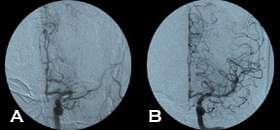

There are two mechanical devices approved by the FDA for use in this situation: they are the MERCI clot retrieval system, and the Penumbra Clot aspiration system.

Both devices are navigated into the blocked brain blood vessel by entering into the artery at the top of the thigh and using X-ray guidance. The MERCI device is a helical snare which grasps the clot and is then pulled out, and the Penumbra device uses aspiration to suction out the clot. In addition, an FDA off-label use of the rTPA to dissolve the blood clot is done by injecting the drug directly into the clot at a lower dose using the same catheterization techniques.